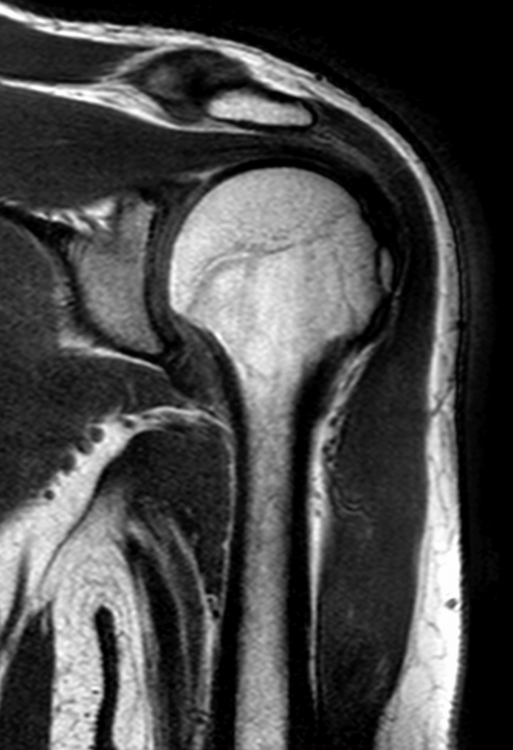

3. Röntgen am Unfalltag: --- MRT nach 6 Wochen (die Bilder habe ich selbst am PC gemacht - mein Arzt hat sie mir vorher gezeigt): --- Röntgen nach 12 Wochen: